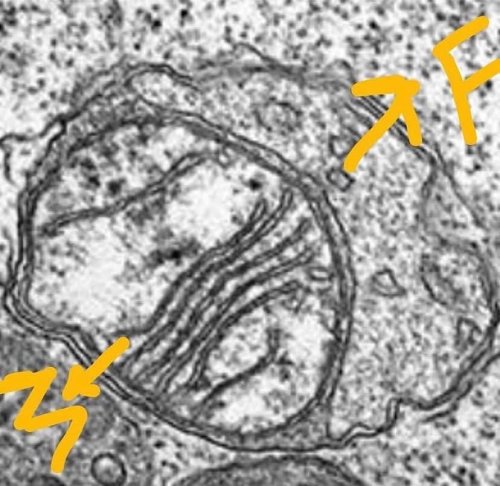

Son zamanlarda sıkça sözü edilen ‘otofaji’ ifadesi var ya, işte otofaji gerçeğinin mikroskop altındaki görüntüsü bu…

Otofaji, kelime anlamıyla ‘kendi kendini yemek’ anlamına geliyor, vücudun kendi kendini yemesi… Fotoğrafta F harfi ile işaretlenmiş yapı ‘Fagozom’ yani ‘yiyen hücresel eleman’, M harfi ile işaretlenmiş olan ise eski, işlevini yitirmiş bir ‘Mitokondri’, yani iç içe geçmiş iki hücre gibi gördüğünüz yapılardan; yiyen-Fagozom, yenilen -Mitokondri. Mitokondriler hücre içi solunum aygıtçıklarımız, hücre düzeyindeki enerji jeneratörlerimiz ki bunların yenilenmesi ‘nefes alan hücrelerimiz’ anlamına geliyor.

Bu otofaji işlemi neden gerekli? Vücudumuzda eskiyen veya eskimediği halde hasar gören veya kanserojen etkilerle genetiği değişmiş ve artık bedenimiz için ‘tehlike arzeden’ bütün hücreler, hatta sadece hücreler değil, bu fotoğraftaki mitokondri gibi hücre içi aygıtlar bu yöntemle yok ediliyor ve yok edilmeyle de kalmıyor, muhteşem bir hücreler arası sinyal sistemi ile kök hücrelere ‘ben gidiyorum, yenisini yap!’ sinyali, hücresel ‘emri’ veriyor… Böylece ufak ufak, mikro düzeyde yenileniyor ve her dem ‘yeniden yaratılıyoruz’ mikron, mikron…